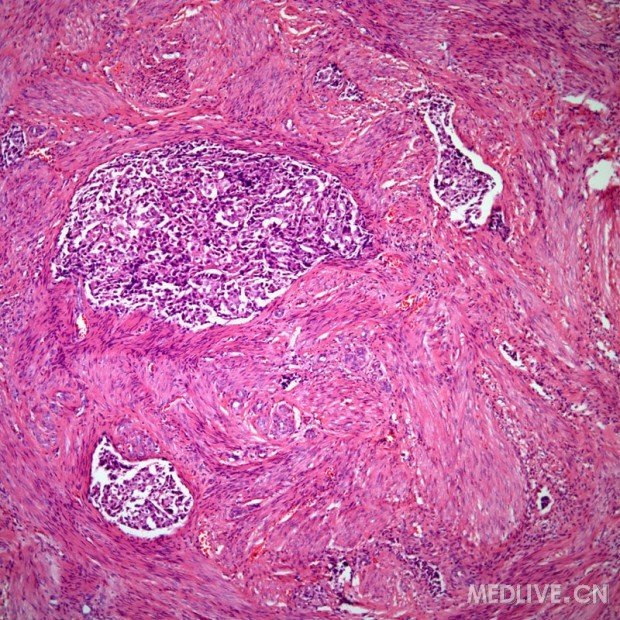

常见浸润性乳腺癌

图片转移性乳腺癌病理学图片

乳腺癌病理he切片